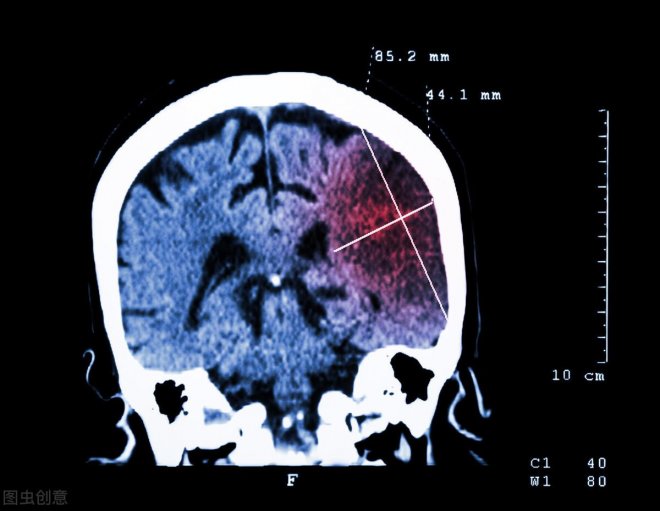

通過檢查,醫生髮現鄧先生所罹患的其實是急性腦梗,更糟糕的是,竟然還是大面積腦梗,鑒於病情危重,鄧先生被立刻送進重症監護室治療,遺憾的是,雖然醫生盡全力搶救,但僅僅一周後,鄧先生還是不幸離世。

脑梗死又称脑梗脑梗塞,是指大脑中的某个组织区域出现坏死情况。它是由向大脑供应血液和氧气的动脉阻塞或狭窄所导致。由于血液供应受限,则会导致缺血性中风,如果血流在相对较短的时间内没有及时恢复,就会出现梗塞